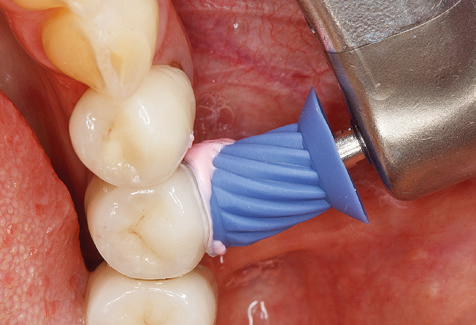

Nach der maschinellen Reinigung der Zahn und Implantatoberflächen erfolgt eine manuelle Instrumentierung der natürlichen Zahnoberflächen mit konventionellen Handinstrumenten. Bei der manuellen Reinigung ist insbesondere auf einen korrekten Anstellwinkel, eine ausreichende Schärfe, eine gute Abstützung und auf eine von apikal nach koronal gerichtete Arbeitsweise der Kürette zu achten. Zur Nachinstrumentierung der Implantatkonstruktionen sollten entweder Titan oder Carbonküretten verwendet werden (Abb. 8). Ergänzend zum Einsatz von Ultraschallgeräten können in der Erhaltungstherapie auch Pulverstrahlgeräte genutzt werden. Dabei ist jedoch zu berücksichtigen, dass diese Verfahren nicht zum Entfernen harter Beläge geeignet sind und daher die Verwendung von Hand oder Ultraschallinstrumenten nicht komplett ersetzen können. Abschließend erfolgt in jedem Fall eine mechanische Politur der zugänglichen Zahn und Implantatoberflächen mit Polierkelchen und Polierpasten (Abb. 9).